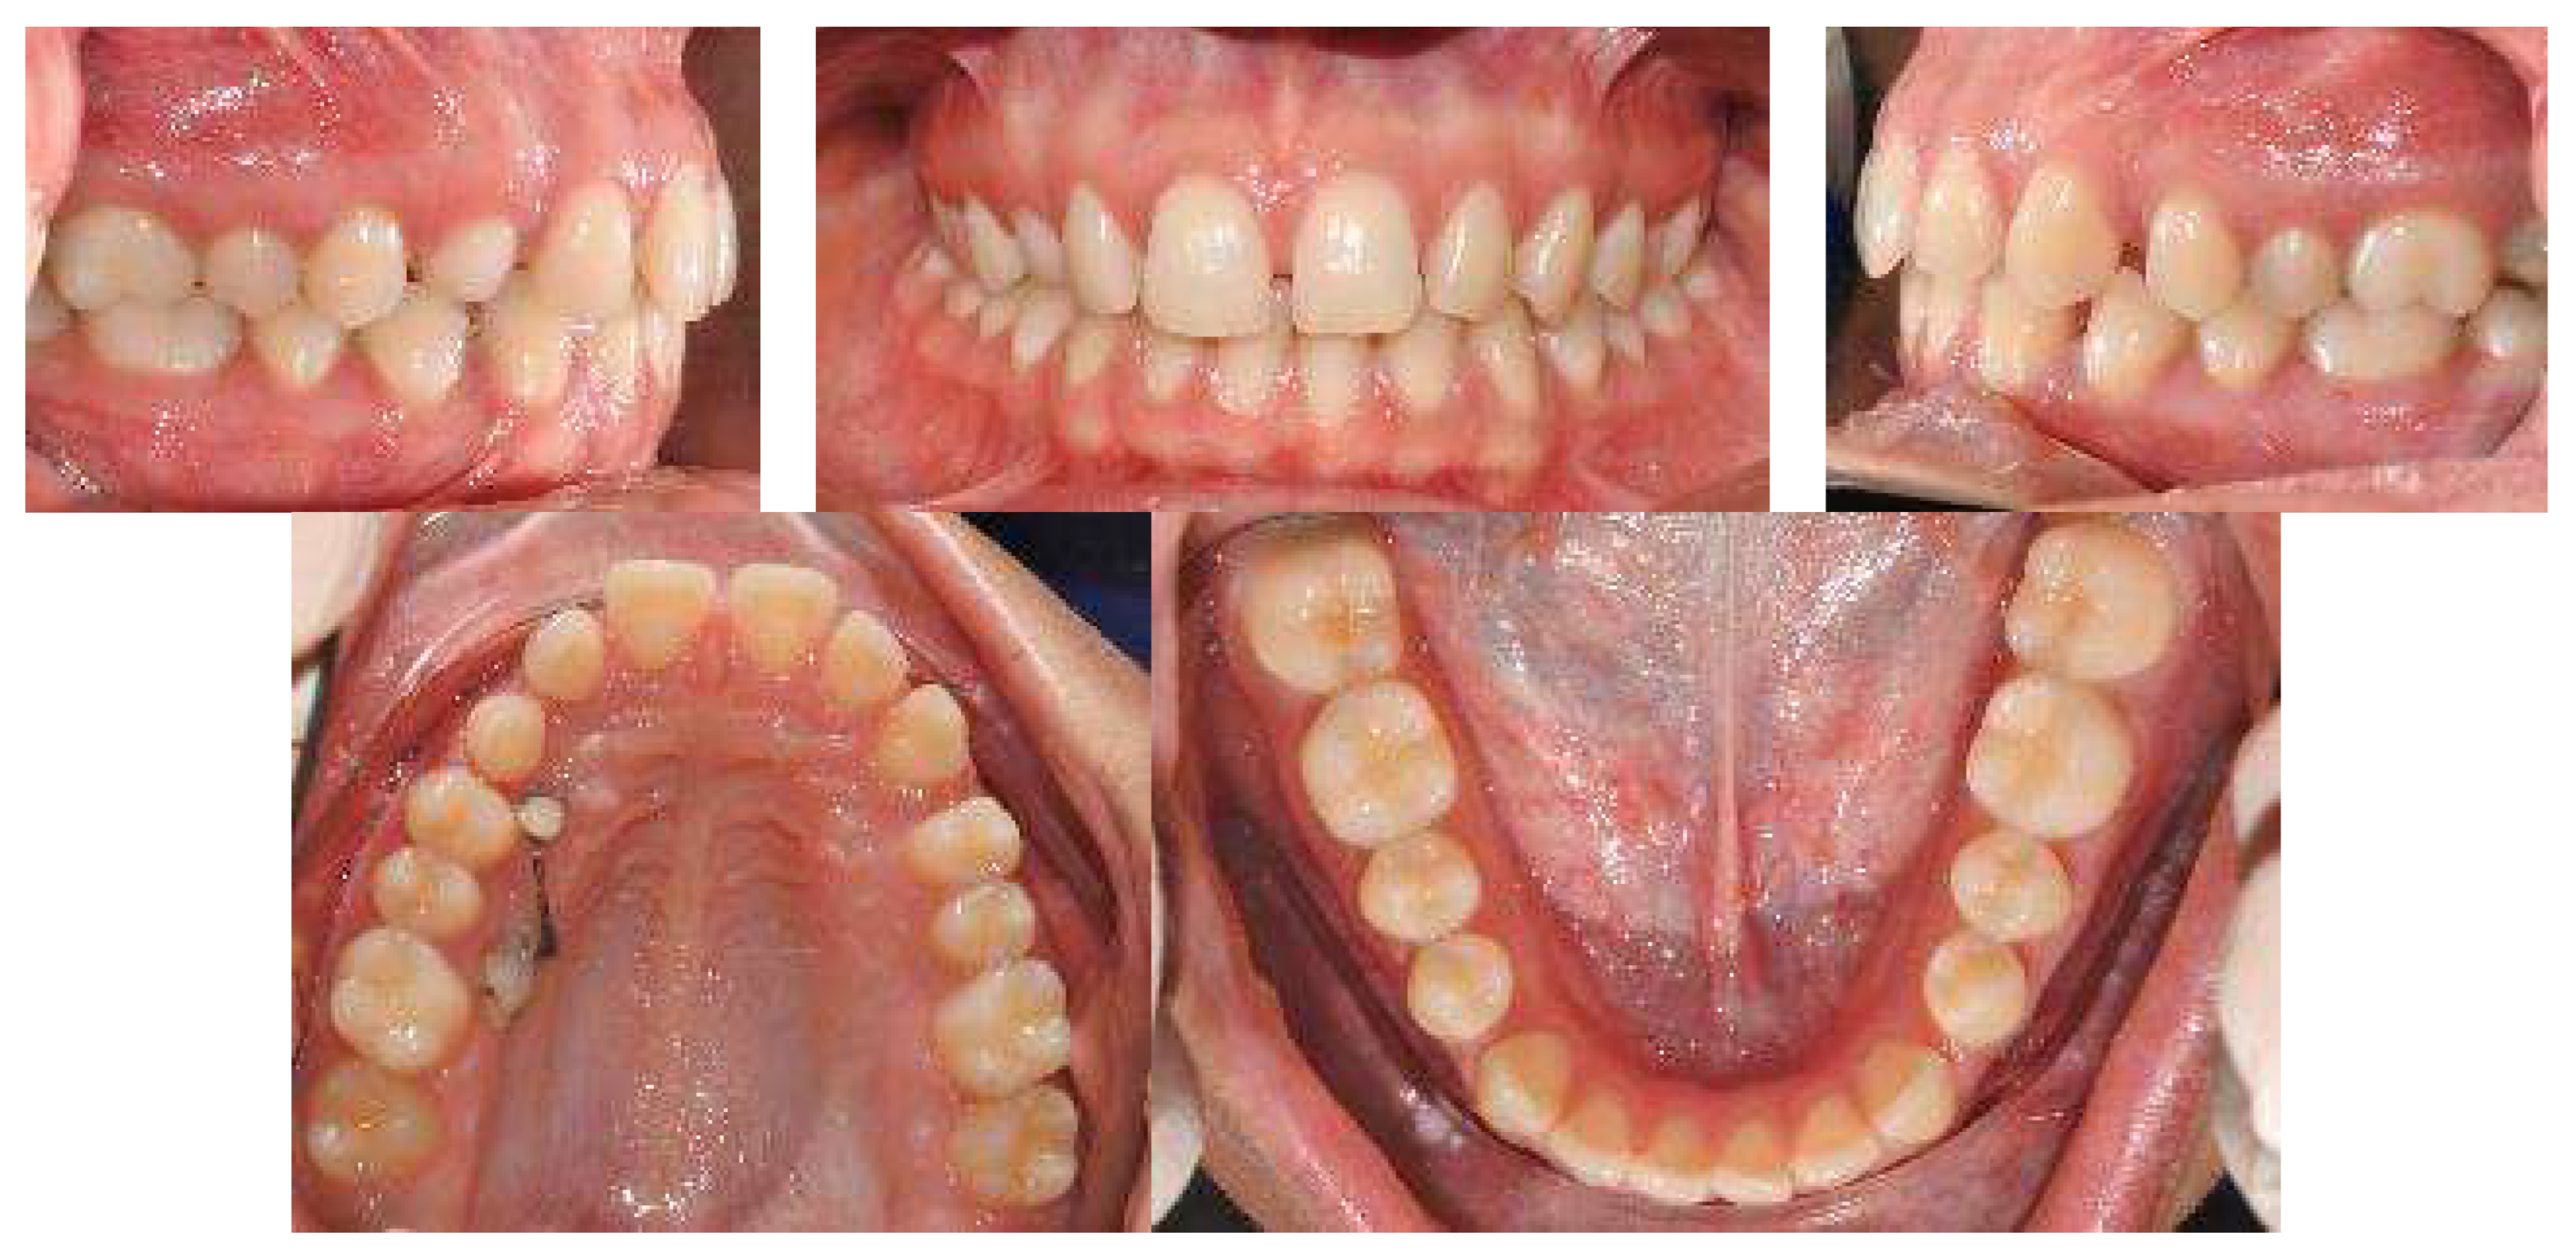

A 17-year-old female patient came for an observation in good general and oral health without any significant pathologies.

The chief complaint of the patient was the absence of a permanent maxillary canine. Her face, from a frontal view, appeared well-proportioned in the three-thirds with facial symmetry.

From a lateral view, the profile appeared straight and a normal nasolabial angle, labiomental sulcus, and lip competence was represented. The initial records were collected and X-rays were taken (Figure 1).

Intraorally, the patient had Class I molar and canine relation on both sides, along with normal overbite, overjet, and the retention of the deciduous canine.

The cephalometric analysis showed a skeletal Class I (ANPg +1.7°) with a good proportion of the maxillaries (SNA 84°; SNB 82.3°) in a normo-divergent vertical pattern (SN^Go-Gn = 32.8°) and a good inclination of the upper and lower teeth, respectively (I/ANS-PNS 116.2°; i/GoGn 91.6°) (Table 1).